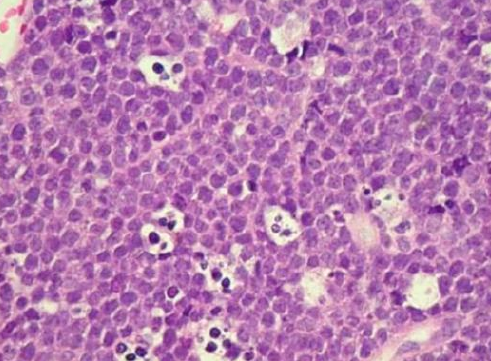

Diffuse Large B-cell Lymphoma (DLBCL)

- 成人口內最常見 Lymphoma (20%)

- 40-50y

- 快速增長,並在淋巴結及其他器官(例如肝臟、脾臟或骨髓)形成腫瘤。

- IHC: BCL6, CD10, MUM1